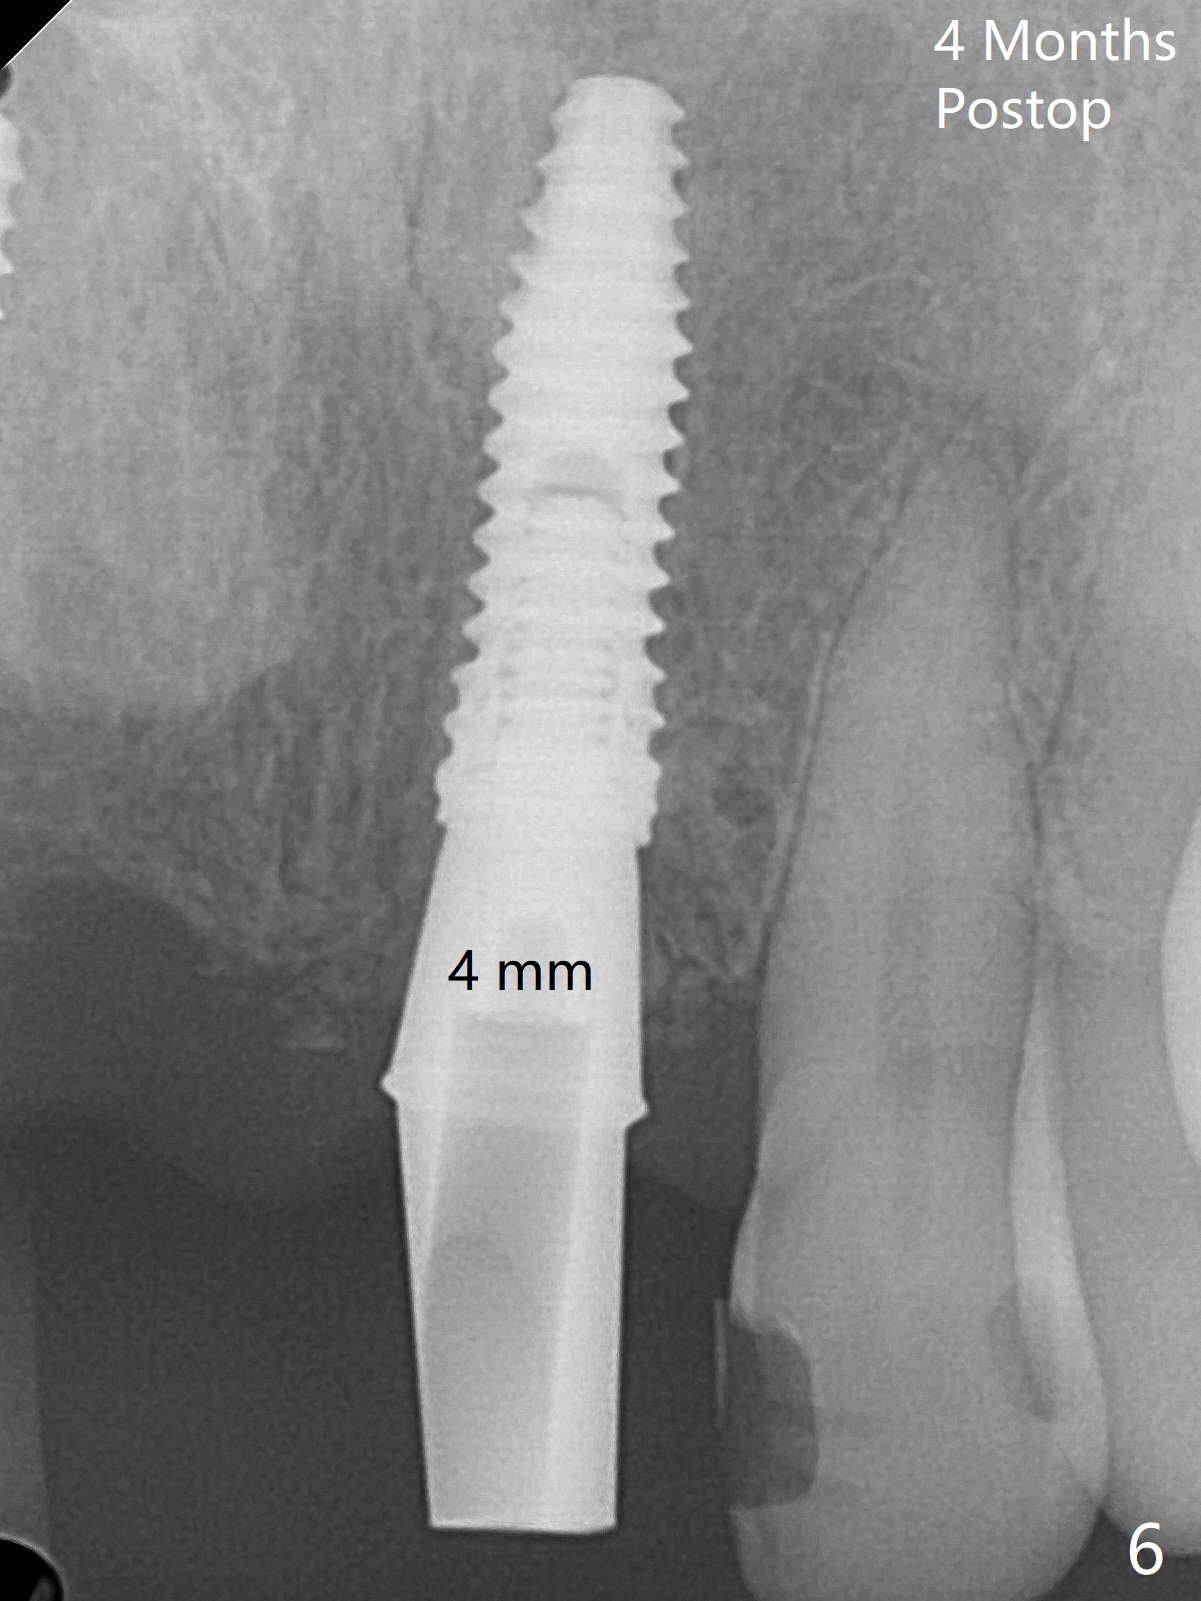

Since the pontic (Fig.1 #8) of the existing failed FPD has severe buccal concavity (*), socket shield is performed when #7 and 9 are extracted (Fig.2,3 *). Angled abutments are placed when 3.5x13 mm implants are inserted with guide. An immediate provisional FPD is fabricated. Acrylic is added to the pontic of the temporary FPD (Fig.4 arrow) to form a concave pontic gingiva (blanch)16 days postop. The patient returns 3.5 m postop with concern over temp being bulky and turning yellow. With Cetacaine and 1-0 cord, labial reducion is done for 7,9 abutments as well as 7 incisal reduction. The provisional is relined to increase 7 8 crown length. Next visit we will continue modification of temporary. Photos will be taken before and after modification (buccal and incisal views). The patient complains of occasional pain at #7. Check whether the socket shield at #7 is a culprit. In fact the implant at #7 is normal. Manipulation of the provisional does not help cosmetics much. A permanent restoration is delivered 5.5 months postop (Fig.7-9).